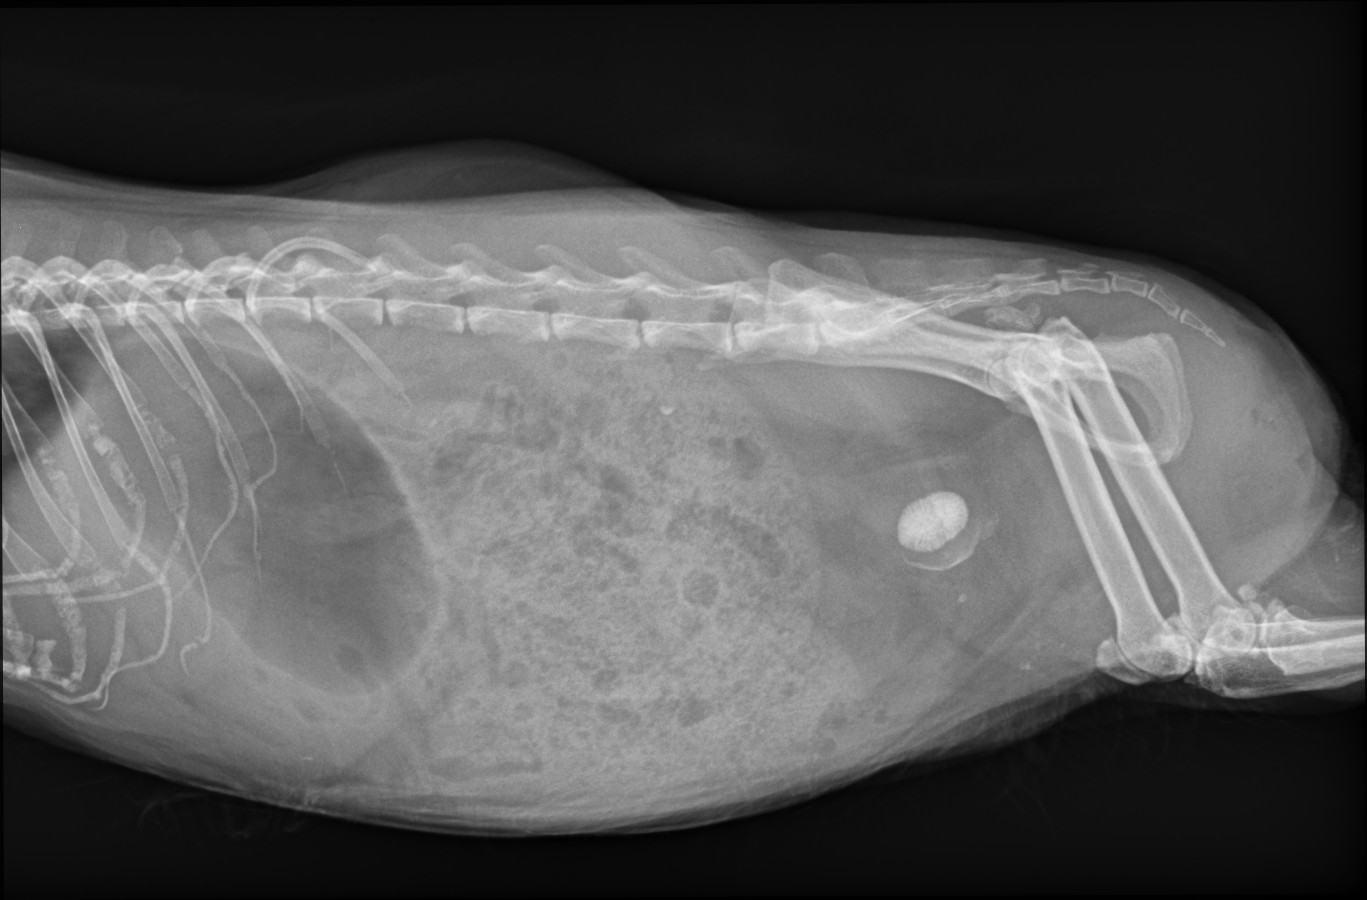

Bei der Untersuchung fiel auf, wie schmerzhaft sie war. Wie geplant nahmen wir Blut ab. Urin ausmassieren ging nicht, sie hat nur geschrien. Im Schall war ein außergewöhnlich großer Schallschatten zu sehen und die Gebärmutter war flüssigkeitsgefüllt. Option CT um mehr zu sehen war also raus, denn wir müssen eh operieren. Es war nun unsicher, ob es ein Blasentumor oder ein großer Stein ist. Ich wusste nicht, worauf ich hoffen soll. Es war ein sehr großer Stein. Also Operation, denn einschläfern war keine Option. Am Dienstag, dem 30.07. wurde ich Ilse eingeschoben. Zusätzlich hatte Madame natürlich wieder beidseitig eine schlimme Bindehautentzündung.

Sind das 3 Steine gewesen oder war es 1, der zerfallen ist? Auf dem Röntgenbild sah es ja nur wie 1 großer Stein aus.

Es war ein großer Stein, der ist beim Zeigen gebrochen. Die Ärztin war froh, dass das nicht in Ilse passiert ist, weil sonst kleine Splitterchen die Heilung gestört hätten.